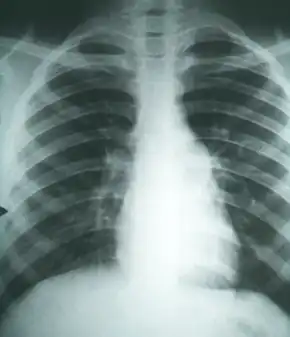

Imaging

Chest X-rays rarely demonstrate nodules or cavities in the lungs, but these images commonly demonstrate lung opacification, pleural effusions, or enlargement of lymph nodes associated with the lungs.[1] Computed tomography scans of the chest are more sensitive than chest X-rays to detect these changes.[1]